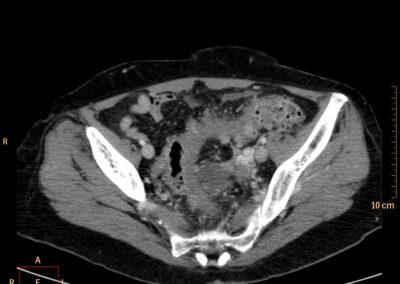

ΕΚΚΟΛΠΩΜΑΤΑ ΠΑΧΕΟΣ ΕΝΤΕΡΟΥ Posted by ΙΠΠΟΚΡΑΤΕΙΟ ΙΩΑΝΝΙΝΩΝ | Dec 16, 2020 | ΠΕΠΤΙΚΟ | 0 ΚΛΙΝΙΚΑ ΣΤΟΙΧΕΙΑ – ΙΣΤΟΡΙΚΟ υποτροπιάζοντες επαναλαμβανόμενοι πυρετοί κυρίως απογευματινές ώρες ΕΡΓΑΣΤΗΡΙΑΚΟΣ ΕΛΕΓΧΟΣ ΑΠΕΙΚΟΝΙΣΤΙΚΟΣ ΕΛΕΓΧΟΣ διακρίνονται τα αποστήματα στην ελάσσονα πύελο, καθώς και εκκολπώματα με εικόνα πάχυνσης του τοιχώματος του σιγμοειδούς ΣΥΖΗΤΗΣΗ